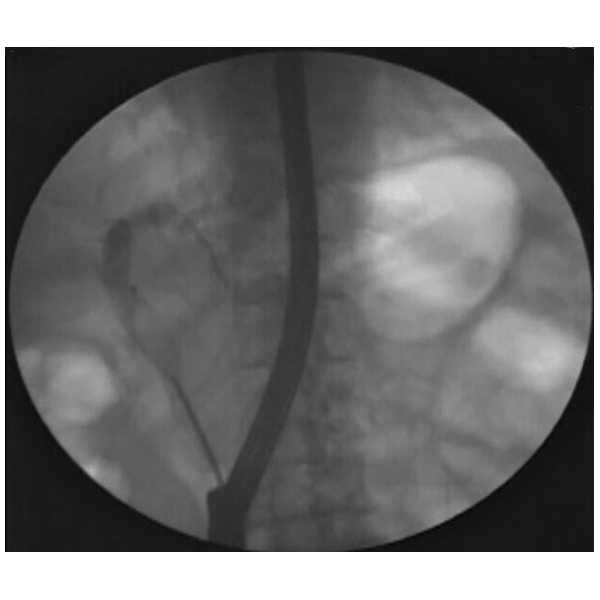

Fluoroscopy image showing Trapezoid RX Retrieval Basket capturing a stone in the common bile duct (CBD)